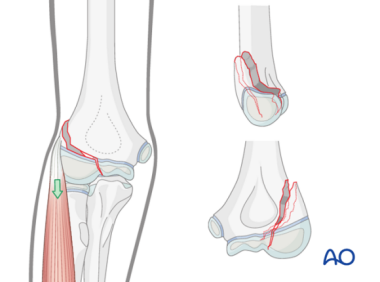

致伤机制:主要分两种,一是牵拉机制(手部伸展、前臂旋后、肘关节伸展时跌倒);二是撞击机制(肘关节遭受外翻损伤时跌倒)。

图2. 伸直内翻应力外侧髁骨折的病理机制示意图。外侧髁骨折块的位移量随着肘部内翻力的增大以及伸肌-旋后肌的收缩而增加。

肱骨外髁:前臂伸肌群的共同起点,强大的肌肉牵拉是导致骨折移位和愈合困难的重要原因。